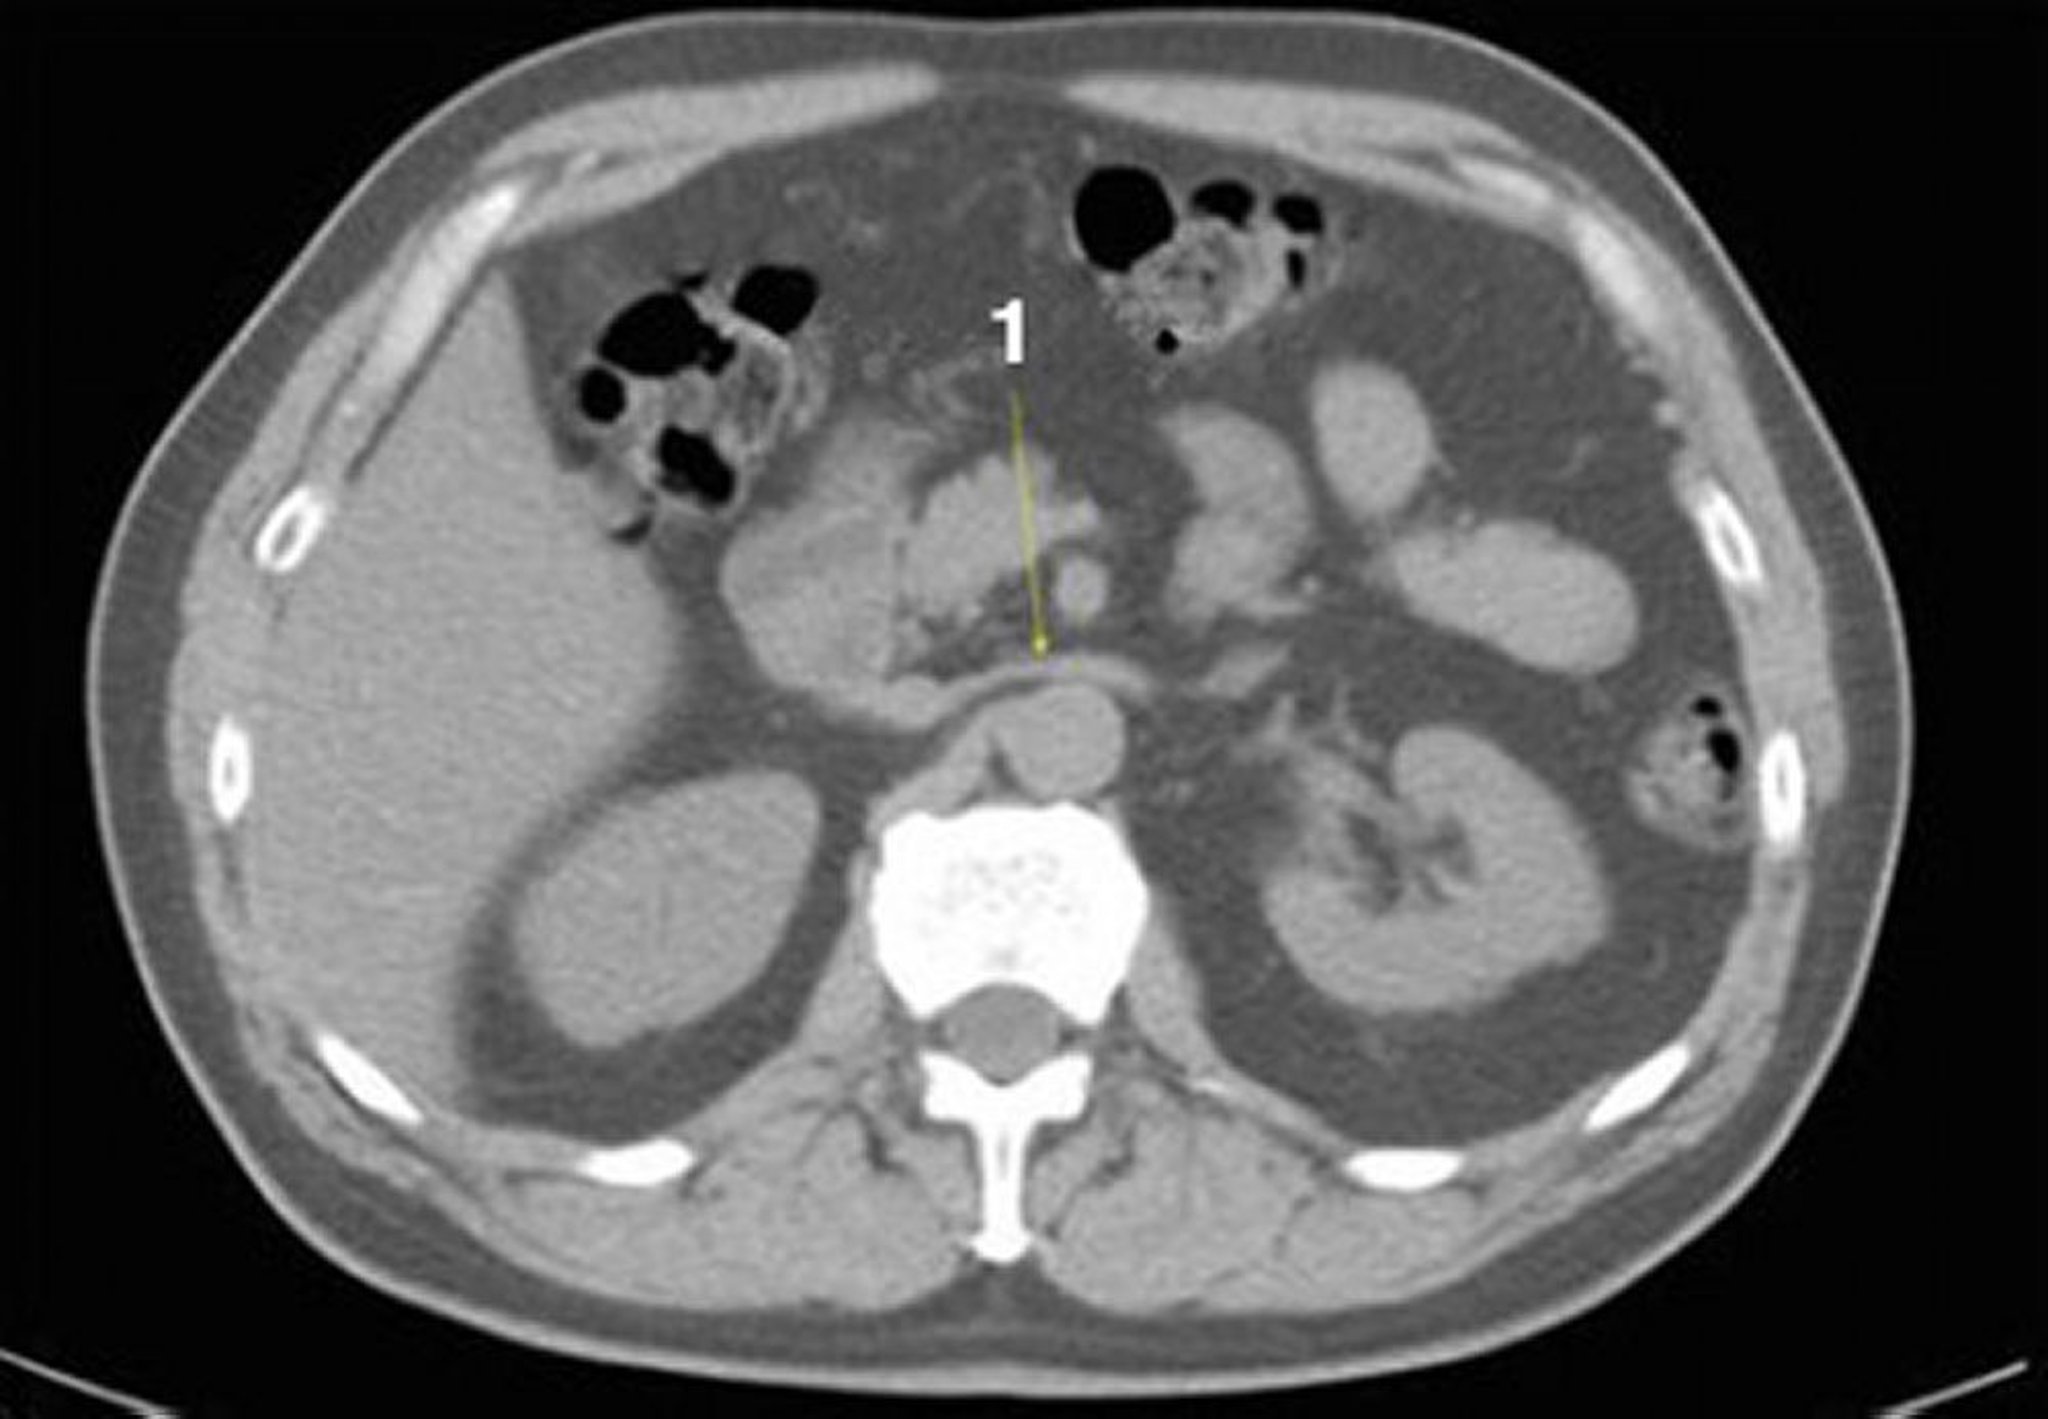

正常解剖を示した腹部および骨盤の単純CT画像(スライド12)

1 = 左腎静脈。